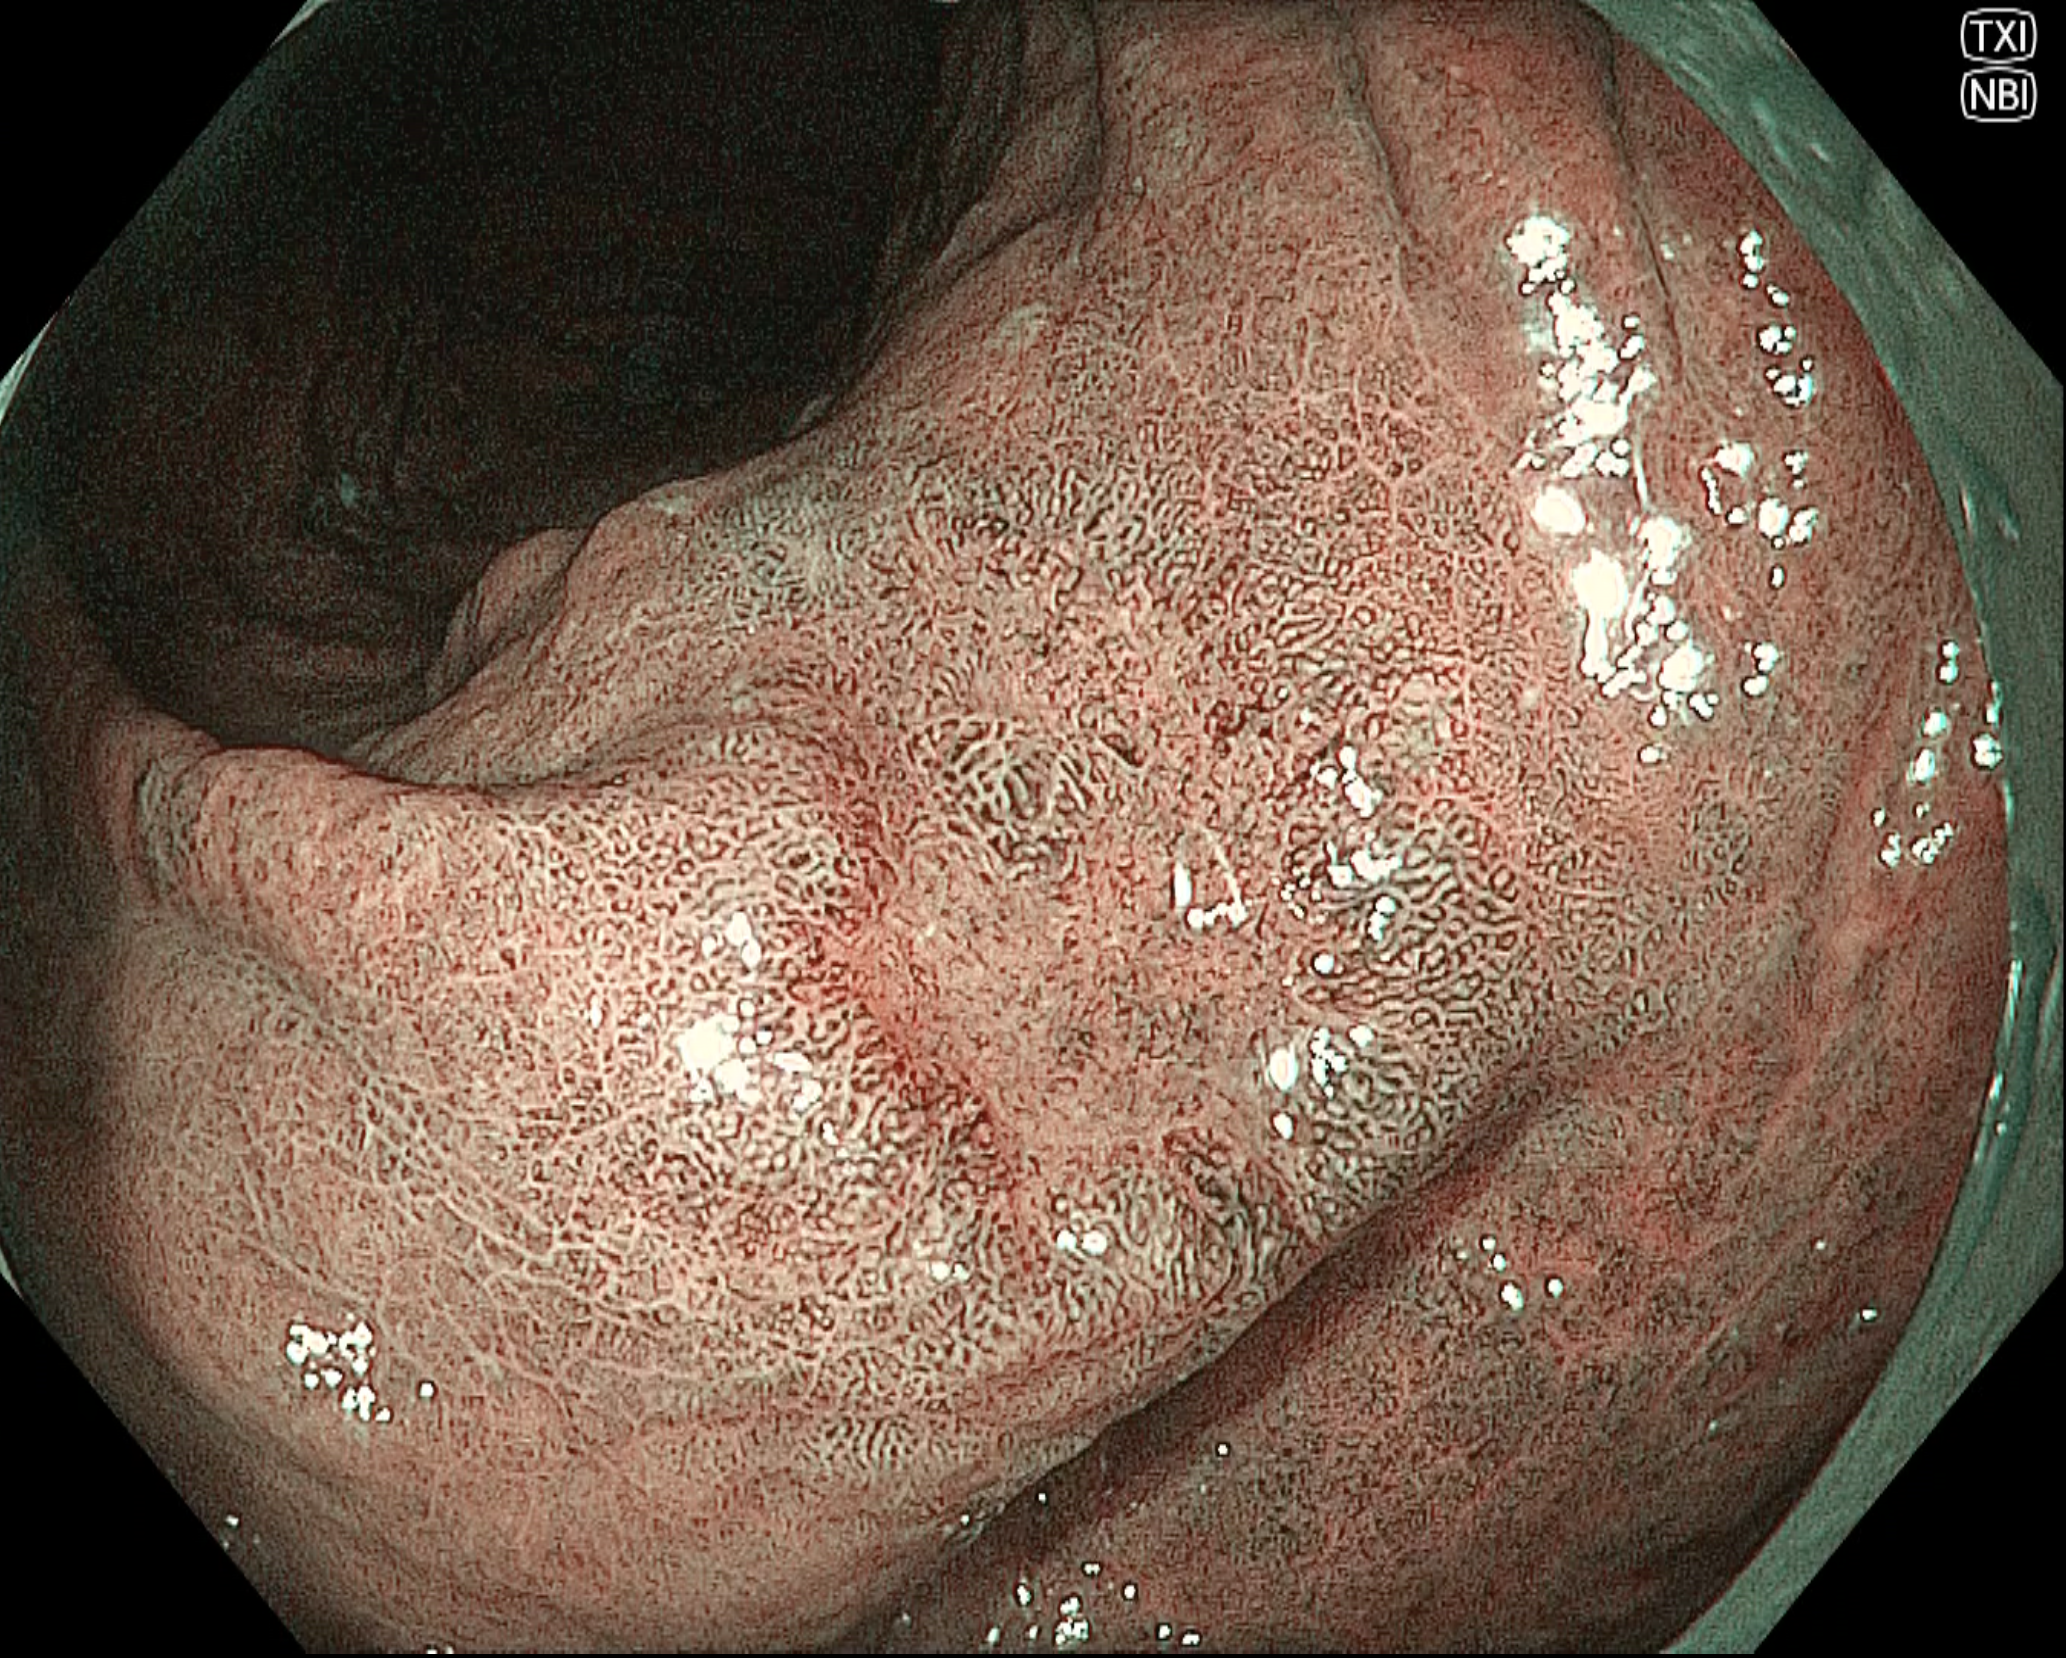

• NBI観察(中遠景)

強調設定:B8

図1

NBI観察では陥凹性病変の辺縁隆起部は褐色調を呈しており、白色光観察と比較して病変境界を視認しやすい。